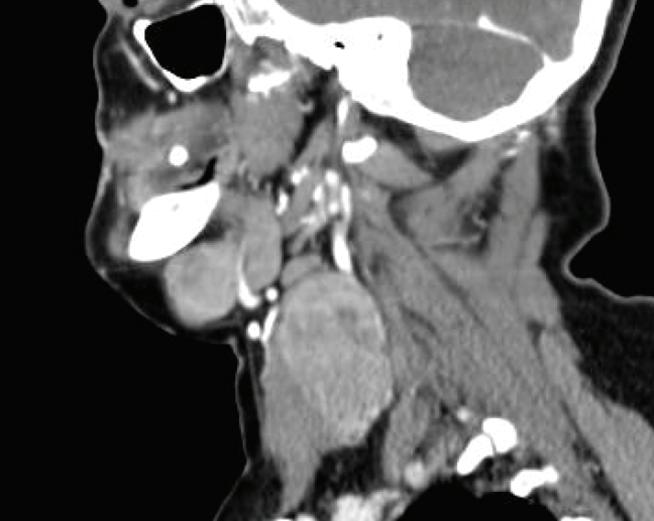

Figura 3: Tomografía con y sin contraste endovenoso realizada 2 años después de la resonancia. En región frontal se observa lesión expansiva, de densidad de partes blandas, que se extiende hacia ambos lados de la calota, que invade la fosa frontal anterior derecha y el seno frontal adyacente con intenso realce tras la administración del contraste endovenoso de tipo heterogéneo compatible con una lesión hipervascularizada. Osteólisis del hueso frontal con patrón permeativo, asociado a áreas de esclerosis óseas con reacción perióstica y remodelación del hueso que se extiende hasta la región del seno frontal y de celdillas etmoidales anteriores. En el parénquima encefálico se observa edema en hemisferio derecho en región frontal y efecto de masa desviando la línea media en la región anterior hacia la izquierda. Servicio de Tomografía de Diagnóstico por imágenes, Hospital de Clínicas “Jose de San Martin”, 2021.

Figura 8. Se realiza tomografía de cerebro y cuello con contraste endovenoso. En región parótida, submaxilar y espacio carotídeo en región infrahioidea derecha, se observan lesiones de densidad partes blandas, con realce intenso, heterogéneo, tras la administración del contraste endovenoso, de tamaño variable, algunos expansivos que generan desplazamiento y compresión de estructuras adyacentes.